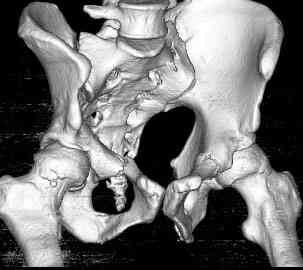

Уважаемые коллеги! опять вопрос по повреждению таза. Больной получил производственную травму 10 дней назад - удар балкой около 3 тонн в область верхней трети правого бедра и лона.

Был диагностирован перелом "типа бабочки" и повреждение уретры. Сделана цистостома. У насв отделении 3 дня. Имеется огромная флюктуирующая гематома с "галифе"-образной деформацией обеих бедер. Пнкционно эвакуировали в несколько приемов из подфасциальных полостей на бедрах около 3 литров геморрагического отделяемого с последующей эластической компрессией. При пункциях выявлено сообщение полостей на бедрах - видимо через поравннуюдиафрагму дна и полость таза - при удалении крови справа уменьшался объем левого бедра. Какой то активности проявялять покабоимся - аппаратная фиксация через отслоенные ткани представляется чреватой нагноением, открытая фиксация в условиях такой гематомы тоже не радует. Хотелось бы услышать ваше мнение

можно полечить в 2 этапа:как правило в области гребней гематомы все же не бывает, если гребни "свободны", то можно ограничиться на первом этапе передней рамой, вводя стержни через них (повреждение ротационно-нестабильное), затем после лечения отслаивающего повреждения Morel-Lavallee, выполнить открытую репозицию, внутреннюю фиксацию, возможно вместе с урологами. Тактику возможного лечения этой

Типичная картина Morel-Lavallee повреждения.

Безуспешны многочисленные шприцевые эвакуации, мы лечим в операционной, доступом на латеральной поверхности, открытием образования с удалением и очисткой полости щеткой. Закрываем с дренажной трубкой (в архивах сайта) и накладывается мягкая повязка Спика из нескольких слоев эластичной повязки.

Следующим этапом через 5-6 дней приступаем к фиксацию повреждения таза, иначе прооперериванные на фоне Morel-Lavallee повреждения осложняются инфицированием послеоперационной раны.

18.12. - отдельное спасибо еще раз А.В.Рункову- больного оперировали (А.В.Рунков) - произведен остеосинтез аппаратом - фиксация за крылья, два стержня в лонные кости и репозиция (почти полная) снимки будут чуть позже.

Дренировали отслойки на бедрах с их санацией. В правой ягодичной области сформировалась зона некроза. Больной "подвешен" за аппарат.